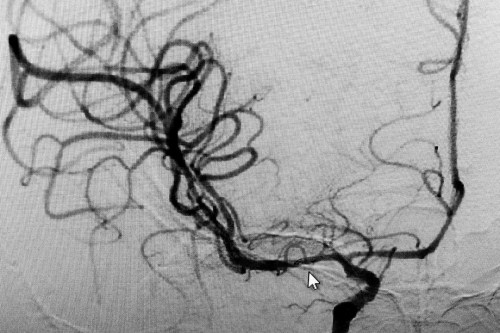

术后DSA血管造影:右侧大脑中动脉开通,并且中度狭窄(光标指向处)